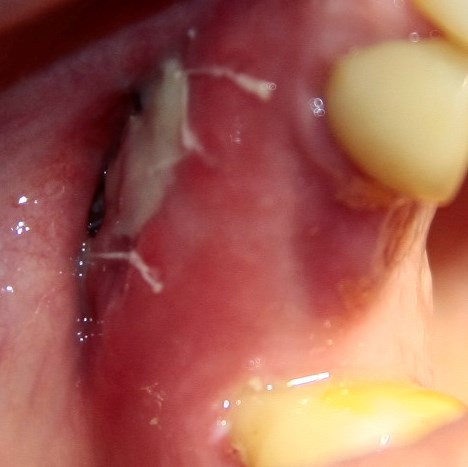

Опыт применения коллагеновой матрицы Mucograft в клинической практике.